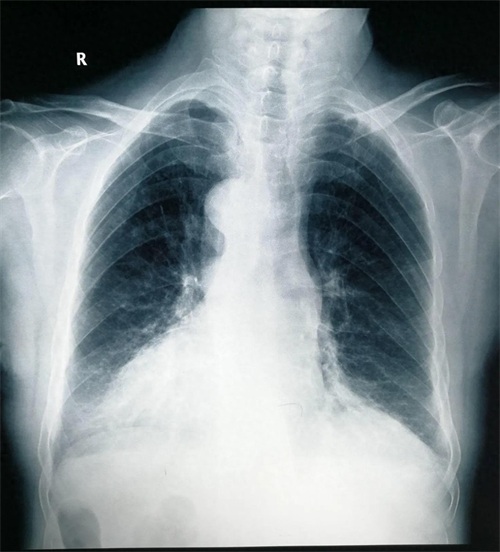

镜面人又称“镜子人”或“镜像人”,是一种极为少见的人体内脏解剖变异,指心、肺、横膈、肝、脾、胃、肠等全部内脏的位置呈180度反位,似正常人的镜面像,而循环、呼吸、消化功能均正常。 为“镜面人”做手术,极大地考验了术者的逆向思维能力,脏器的反位使取石手术难度和手术风险都增大。医生的手术习惯、技巧等也都要跟着一起“转位”。对病人来说,风险也在增大。给“镜面人”做手术,花费的时间远比正常人多。 近日我科收住一例腹腔内脏器反位病人,患者冯某某,年龄81岁,主因:右上腹间断性疼痛不适2月。入院诊断为:胆囊多发结石,急诊胆囊炎,主动脉硬化,三尖瓣反流,冠心病,心肌缺血,频发室性早博,同时合并有胸椎结核(T9-10)。患者年龄偏大,基础病多,手术风险大,行腹腔镜下胆囊切除术。